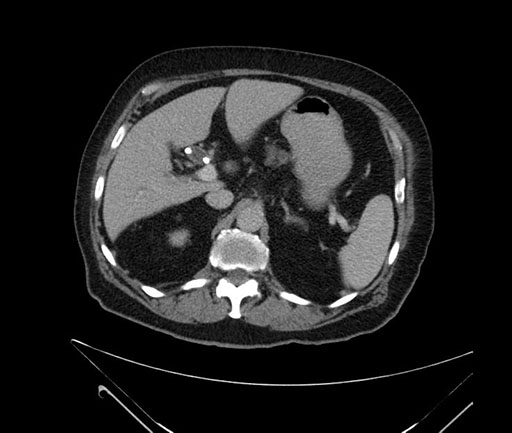

Imaging Analysis

Look through the patient's CT scan to identify any areas of concern for the necessary procedure.

Based on your CT findings, which issue(s) would give reason for "planned slowing down moment(s)" in this case?